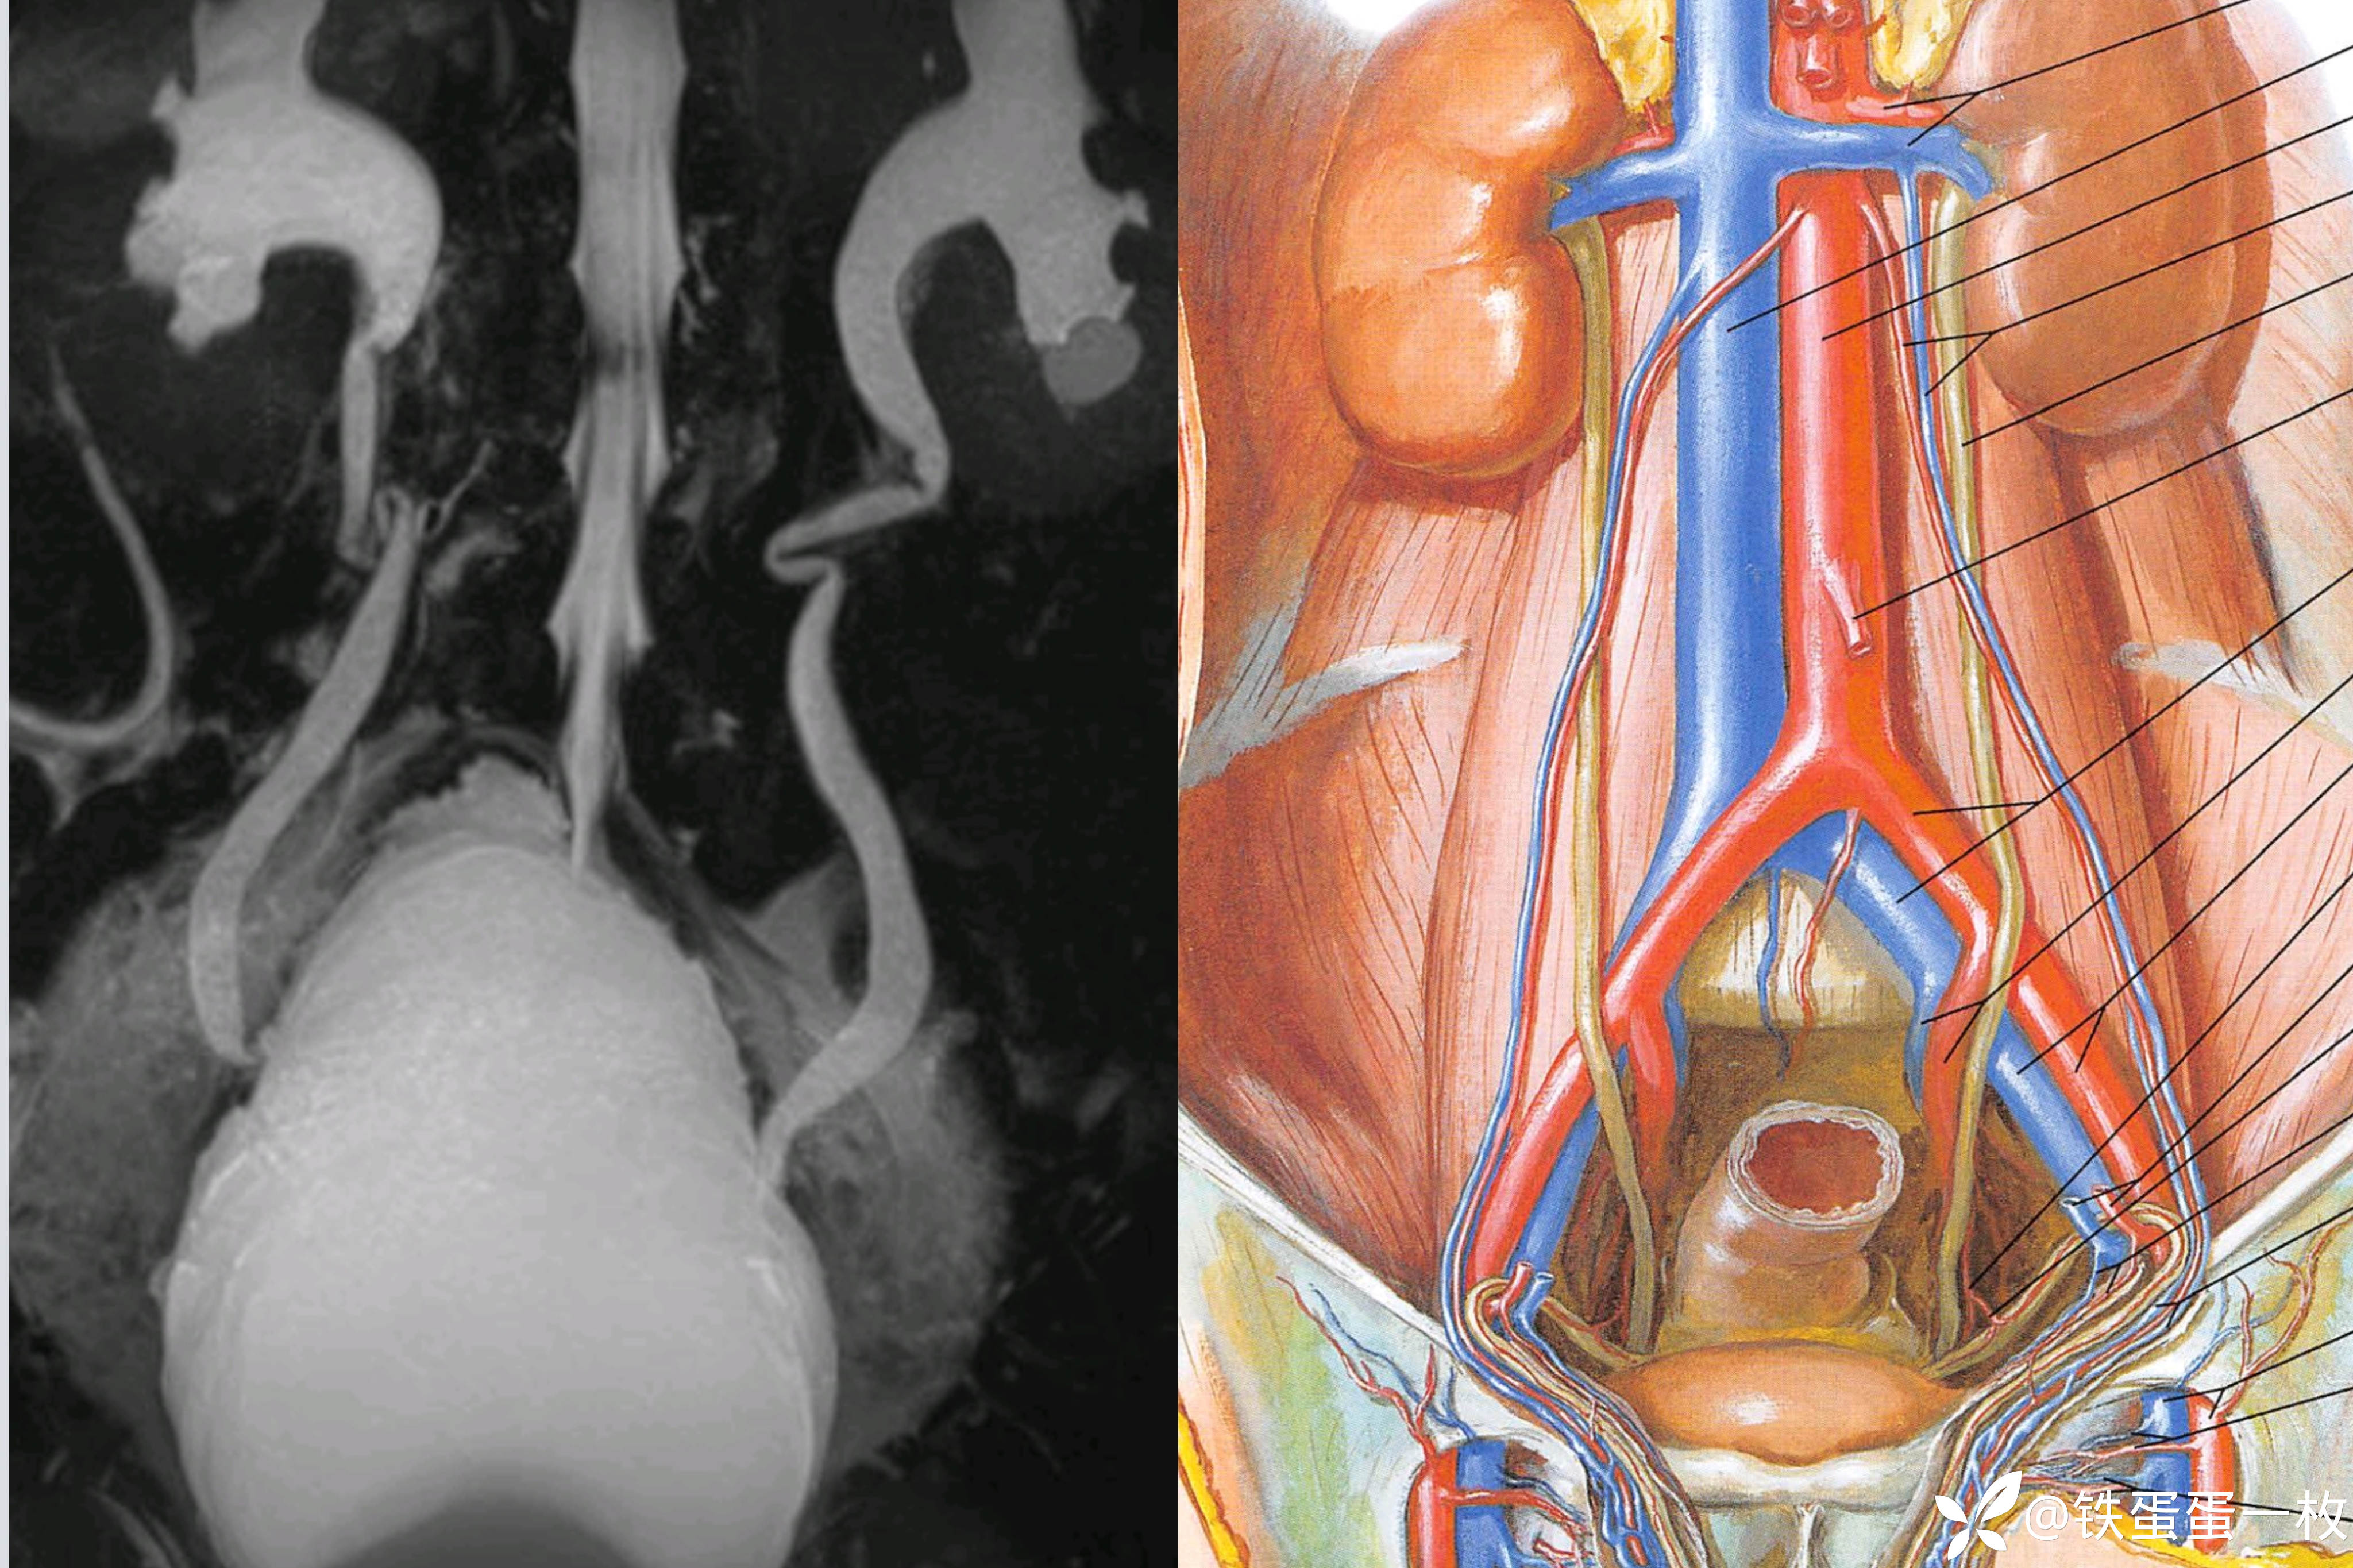

1)CT检查可以发现PL患者多出现较为明显的肾积水,膀胱位置也发生改变;

2)MRI检查可发现膀胱出现变形,位置上抬,可以对盆腔内脂肪的形状、大小进行较为客观的观测。

膀胱位置改变、膀胱壁增厚

膀胱颈部拉长,冠状位呈“梨形”

膀胱尿道造影:梨形膀胱。(这就是核磁影像后面的图片存在的意义)。